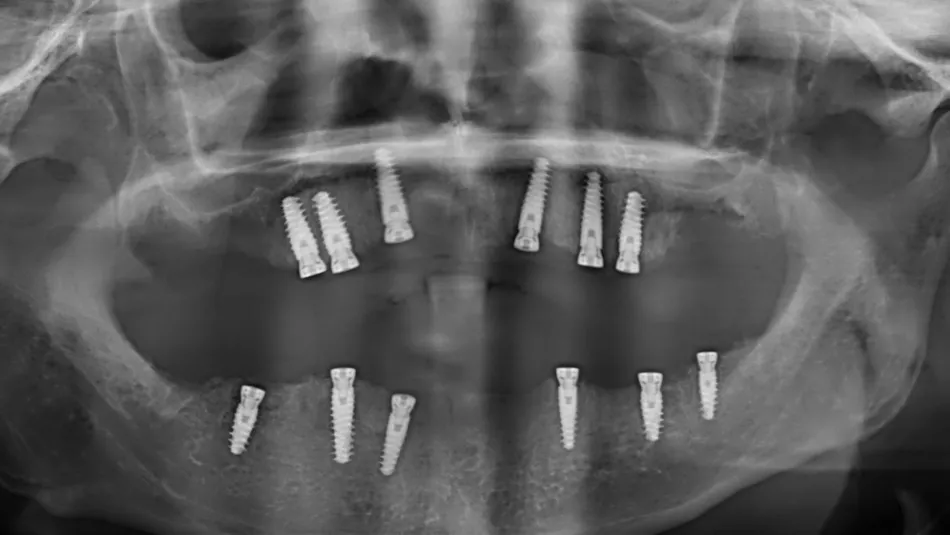

22. Post operative radiographs of the implants and with restorations screwed in place.

22

A total of 6 Axiom X3 ® Tissue Level N platform implants were utilized on the upper jaw, comprising 3 units of Ø 4.0 x 10mm and 3 units of Ø 4.0 x 12mm, all with a gingival height of 2.5mm.

On the lower jaw, 6 implants were used, including 3 units of Ø 4.0 x 8mm, 2 units of Ø 3.4 x 10mm, and 1 unit of Ø 4.0 x 10mm, all with a gingival height of 2.5mm. The average torque measurement at implantation was recorded to be 60 N.cm.